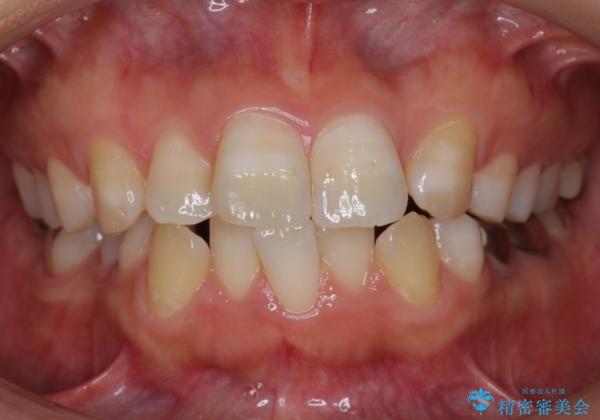

歯のがたつき インビザラインで矯正

- 歯並びを主訴に来院。

左上2番は以前抜歯したとのこと。

奥歯を後ろに下げて、前歯を並べています。

マウスピースと矯正用のミニスクリューを使用して治療しています。

銀歯も白くということでしたので虫歯治療も一緒に行っています。